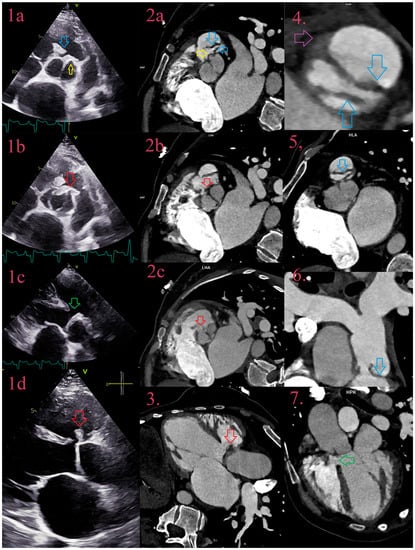

3.7. Pseudoaneurysms

3.8. Fistulas

3.9. Leaks